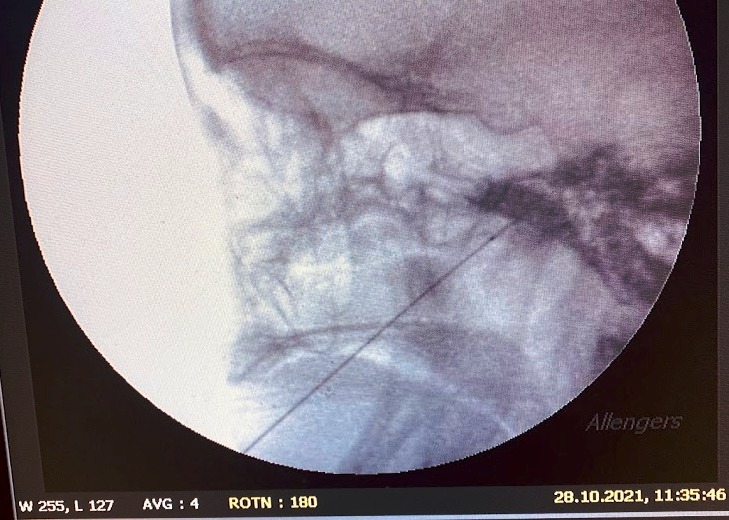

As a compassionate and highly skilled pain management specialist, Dr. Ninadini is committed to the precise diagnosis and multidisciplinary treatment of various pain syndromes. Whether you are coping with chronic back pain, osteoarthritis, or post-operative neuropathic pain, she employs cutting-edge interventional techniques alongside personalized care to deliver optimal therapeutic outcomes.

What is the role of interventional procedures in pain management?

Interventional procedures, such as nerve blocks, radiofrequency ablation, and spinal cord stimulation, play a crucial role in managing chronic pain conditions. These minimally invasive techniques target the source of pain and are often used when conservative treatments are insufficient, providing significant relief and improving the quality of life.